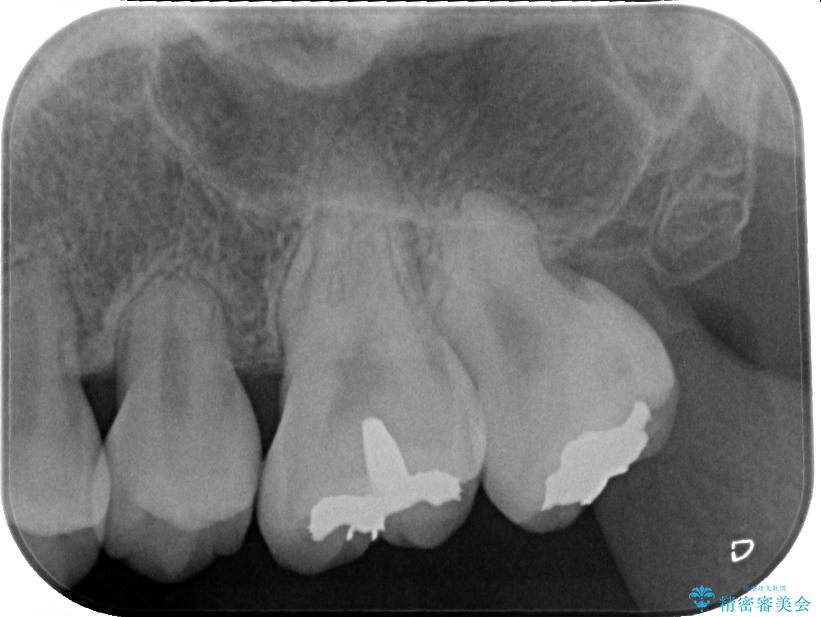

セラミッククラウンの適合はレントゲン写真からも分かる通り、境界がぴったりと合った、高適合のものとなりました。